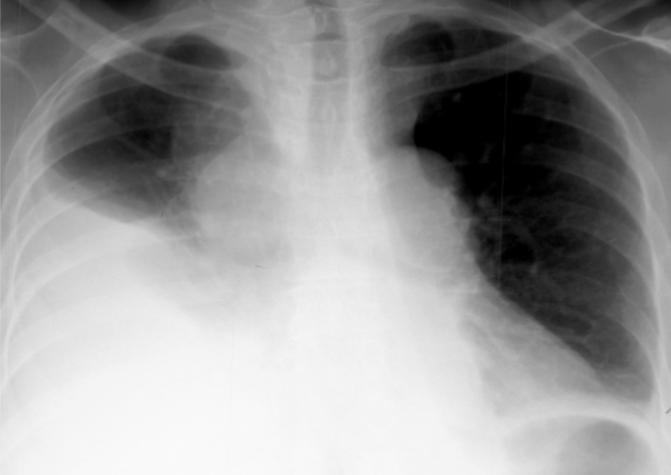

What is this patient presenting with?

Pulmonary edema—classically “Batwing” in appearance

(starts central, spreads outwards)